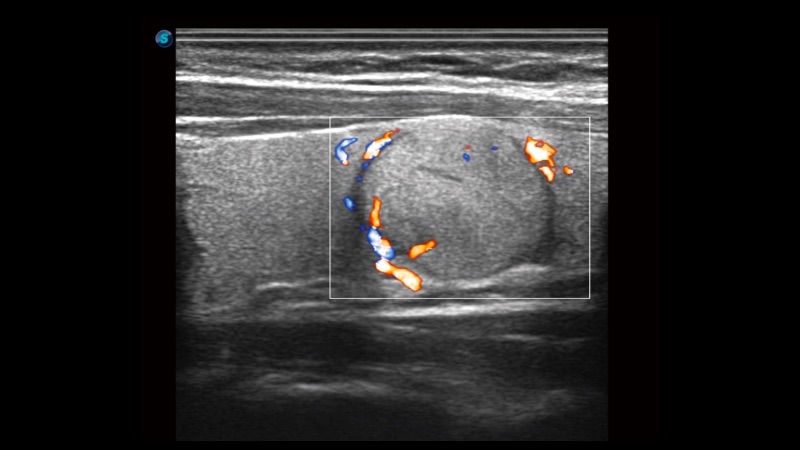

As a new innovative technology, SR Flow improves the capability of detecting low velocity flow signals. It also improves on spatial resolution and overcomes overflow to present users with real hemodynamic information.